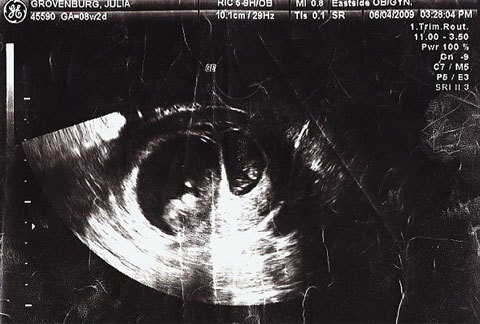

![]() |

| Kết quả đo nhịp tim thai nhi và hình ảnh siêu âm khi mang bầu cho thấy, hai đứa trẻ trong bụng Julia cách nhau khoảng 2 tuần rưỡi tuổi. Ảnh: Double Vision Media. |